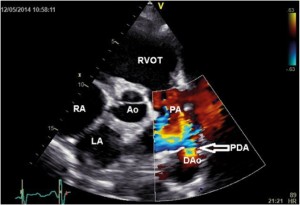

A 33-year-old man who had been diagnosed with PDA in childhood was refferedfor cardiac evaluation for fatigue and progressively worsening dyspnoea on exertion over the past 3 months. Physical examination revealed an afebrile patient, hyperdynamic precordium, a continuous murmur with thrill over the pulmonary area, peripheral oedema and hepatomegaly. The blood pressure was 120/60 mm Hg and the peripheral pulses were prominent. Auscultation of the lungs revealed mild basal crackles bilaterally. There were no clinical stigmata consistent with endocarditis. The ECG showed sinus rhythm at 78 bpm, biatrial abnormality, signs of left ventricular hypertrophy and complete right bundle branch block. There was no inflammatory syndrome or anemia. Transthoracic and transesophageal echocardiography confirmed the presence of a large PDA (defect size 11 mm), with a continuous systolic-diastolic flow signal with high velocities (up to 4.8 m/s) recorded by continuous wave Doppler examination at the level of this turbulent jet from the descending aorta to the pulmonary artery (Figures 1-3). The left ventricle was severely dilated (EDV/ESV=247/124 ml), with mild global systolic dysfunction (ejection fraction of 50%). The assessment of pulmonary artery systolic pressure was carried out by measuring peak tricuspid regurgitation velocity and the estimated value was 52 mm Hg. The TTE exam also revealed mobile vegetations on the pulmonary valve, with severe valve destructions, lack of coaptation and severe, free pulmonary regurgitation on color Doppler examination (Figures 4, 5). No vegetations were seen on the other valves, cardiac chambers or great vessels.

Figure 1. Transthoracic parasternal short axis color Doppler imaging revealed PDA with left to right shunt (arrow); LA-left atrium, RA- right atrium, RVOT- right ventricular outflow tract, Ao- aortic root, PA- pulmonary artery, PDA-patent ductus arteriosus, DAo-descending aorta.